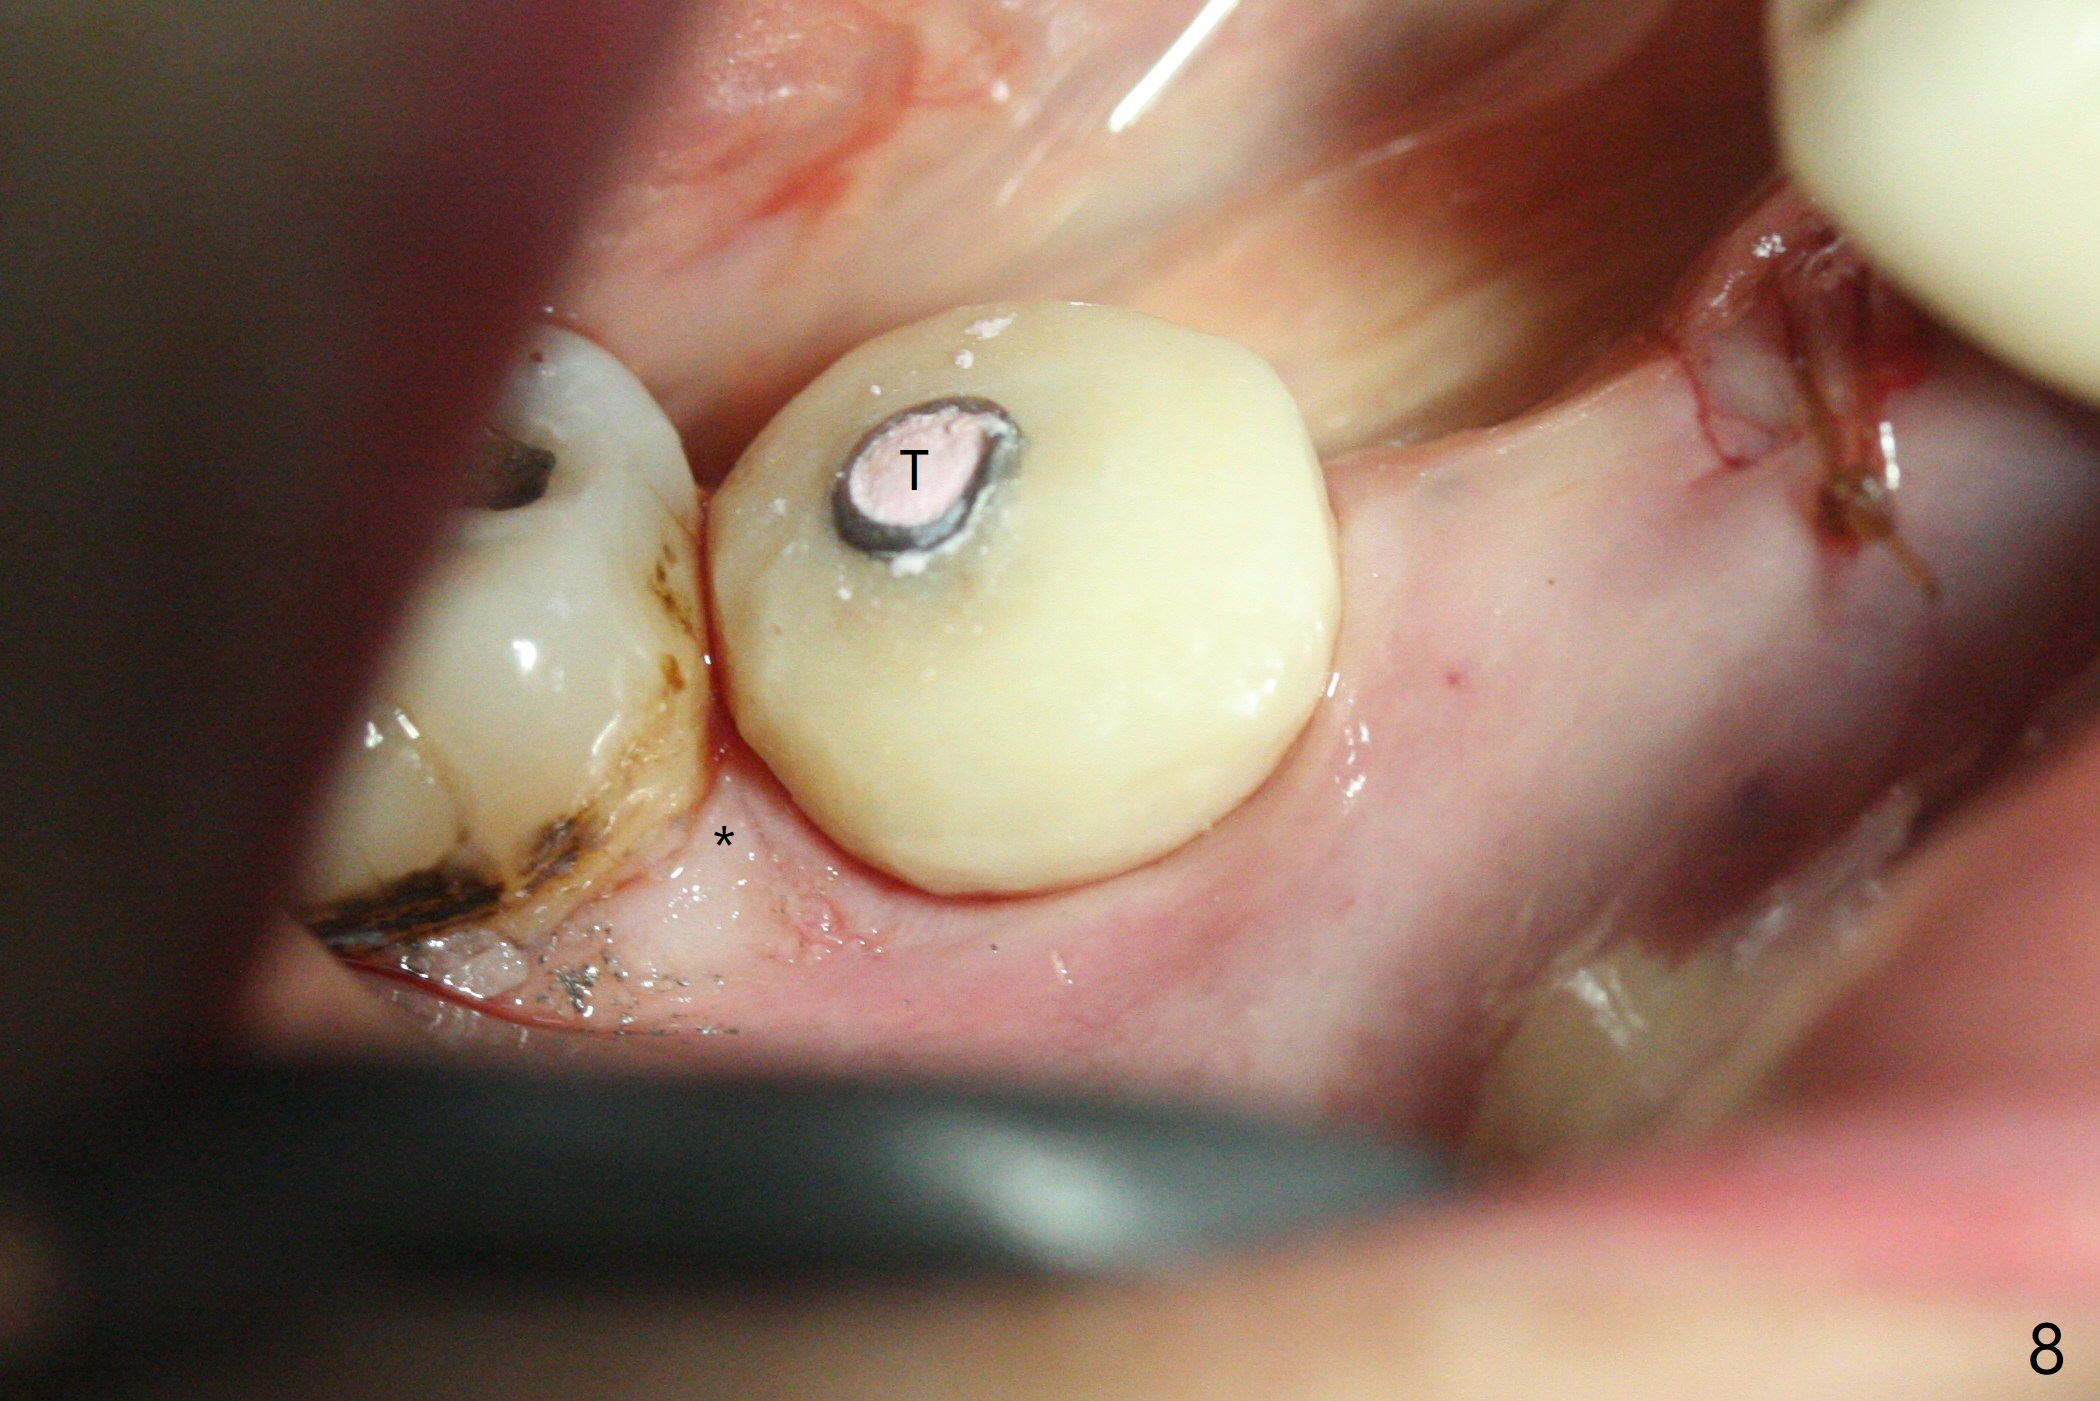

The extraction socket of #31 has a thin septum (Fig.2), which is removed partially with 12 mm bone trimmer (Fig.3). After placement of a 5x9 mm FC implant (~40 Ncm) and 6 mm bone profile drill, a 5.5x4(2) mm abutment is incompletely seated (Fig.5 <) and later is changed to a 4.5x1 mm temporary abutment (Fig.6, 8 T). The latter is used to fabricate a provisional, which in turn supports the distal papilla (Fig.8 *). The gingiva is slightly erythematous immediately post periodontal dressing removal (3 weeks postop, Fig.9). Take CT to confirm whether the cortical drill helps keep the #29 implant lingual. Use a profile drill at #29 if crestal bone loss is not obvious. There is bone coronal to #29 implant 4 months postop (Fig.10). Upon incision, the ridge is rounded (Fig.10'), but the implant appears to be buccally placed (Fig.10'' (post high speed handpiece and 5.5 mm profile drill)). The latter is confirmed by CT (Fig.12, as compared to design (Fig.11)). In spite of use of cortical drill coronally, the implant is still deviated buccally due to contrasting deferential bone density linguobuccally (Fig.13). By comparison, there is no such bone density differential involving an immediate implant at #31; the implant is placed in the socket without contacting the buccal or lingual cortices (Fig.14). The final implant is the same as expected (Fig.15). To avoid implant deviation in the lower premolar region, leave the root in place until osteotomy is finished. Five months postop, the temporary and healing abutments at #31 and 29 change to pair ones (Fig.16). Since there is limited clearance from the crestal bone, smaller abutments are used with the apparently same degree of seating (Fig.17). The abutments are prepared due to the mesial (#31) and buccal (29) tilt before impression.